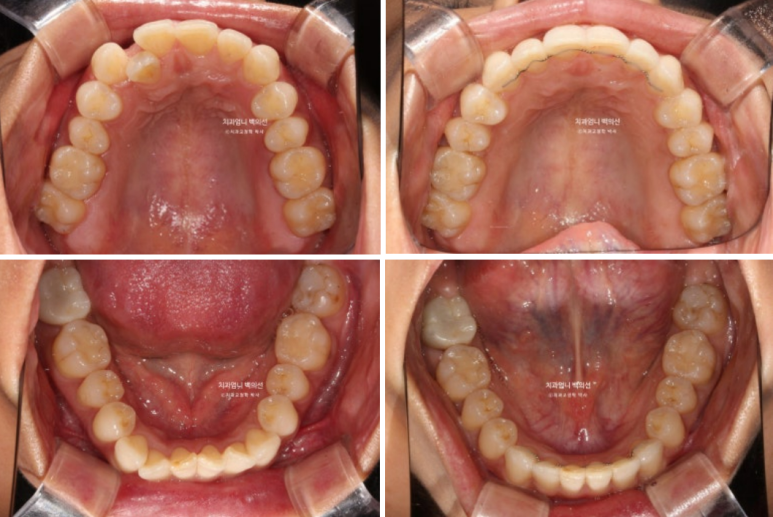

멀리서 오시기에 내원간격 때문에 인비절라인 치료를 선택하셨고 23년 10월부터 24년 8월까지 첫세트 44개 장치를 모두 낀 후 모습입니다

중심선은 잘 맞으나 입천장에 위치했던 축절치가 아직 완벽하게 제자리를 찾지 못했습니다.

덧니의 머리부분은 앞으로 잘 나와 있지만

교합면에서 보면 입천장에 위치했던 덧니 뿌리 부분은 아직 입천장 쪽에 위치해 있습니다.